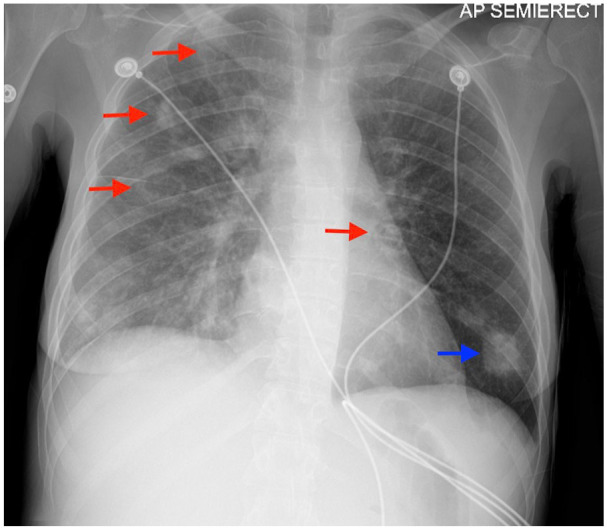

Patients with a history of drug abuse and right-sided endocarditis are particularly susceptible to developing septic pulmonary emboli. Rarely, septic pulmonary emboli can cause severe lung injury resulting in parenchymal loss despite appropriate antibiotic therapy. We present 2 cases of severe lung injury associated with septic pulmonary emboli stemming from right-sided infective endocarditis, emphasizing 2 rare complications: bilateral spontaneous pneumothorax and pneumatocele formation.

Abstract Image